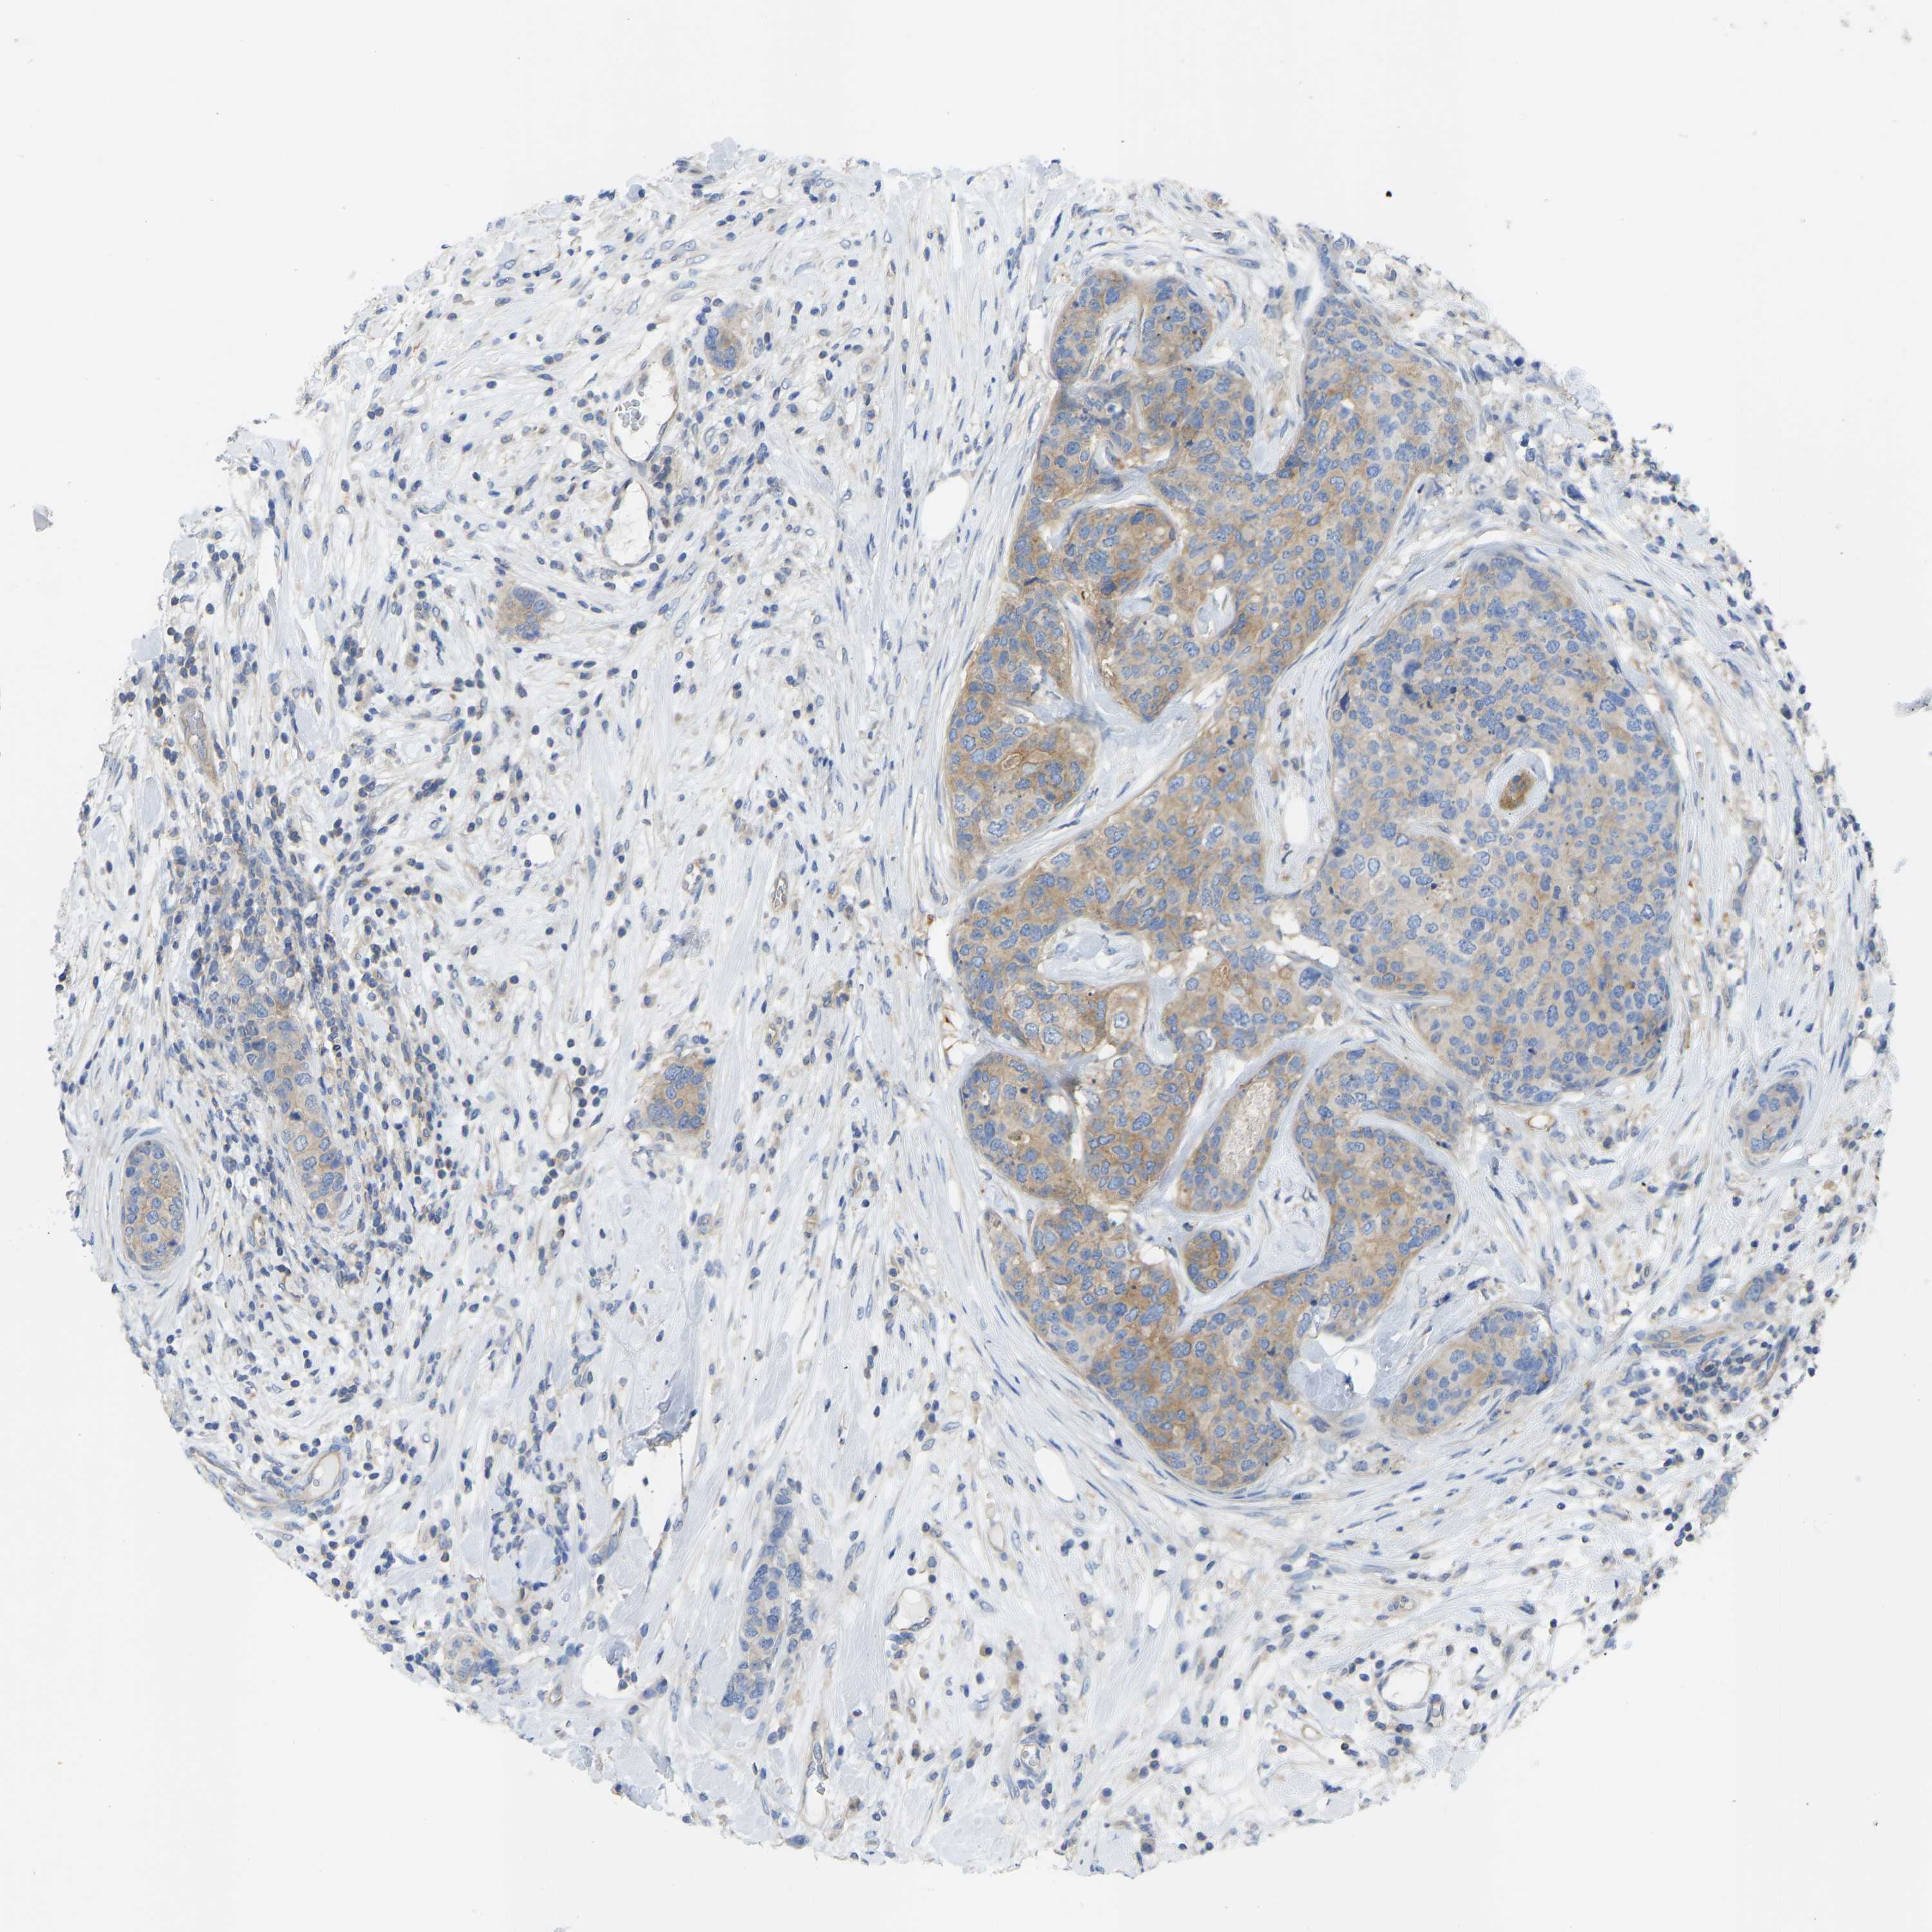

CANCER BREAST CANCER Show tissue menu

BRCA TCGA BRCA VALIDATION PROTEIN EXPRESSION